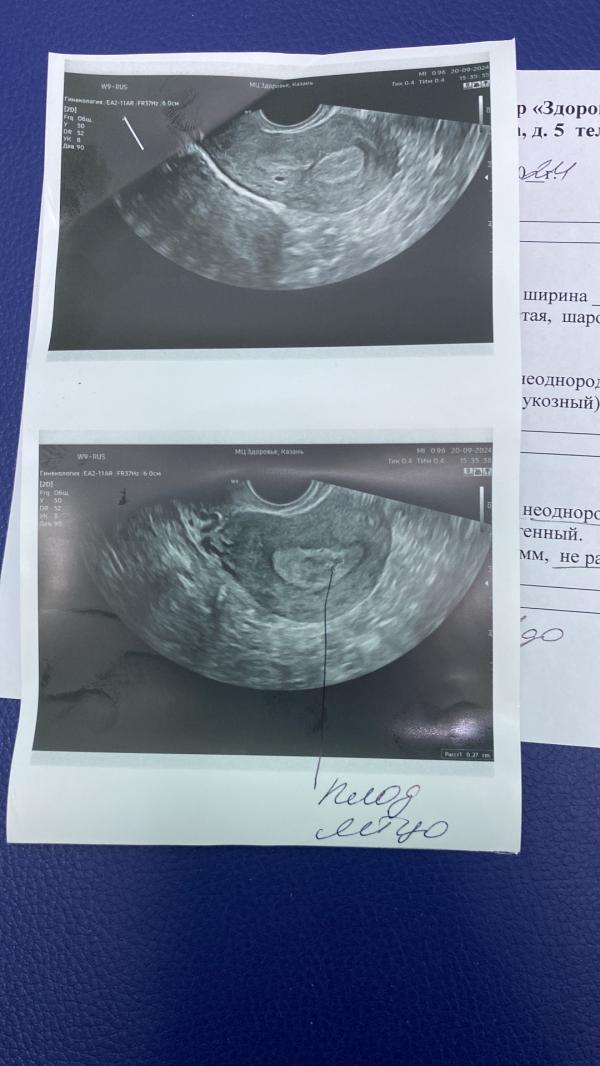

Что показало УЗИ?

Сделала узи может было у кого такое как все прошло?

Ставят не развивающуюся беременность